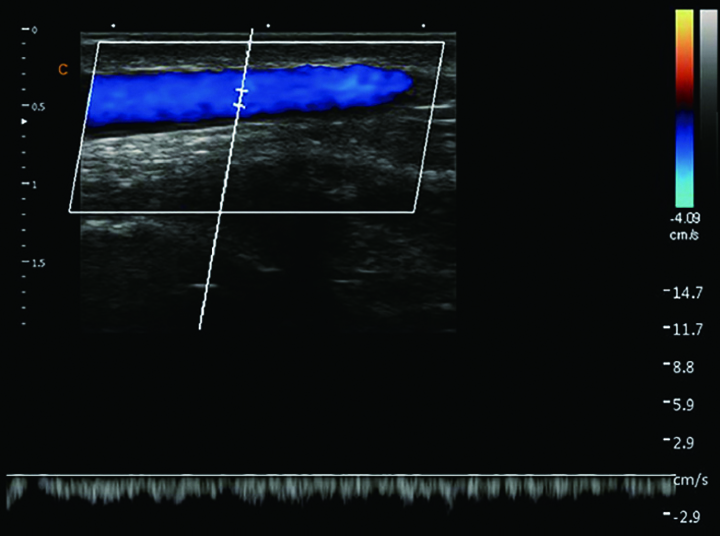

贵要静脉,脉冲多普勒模式